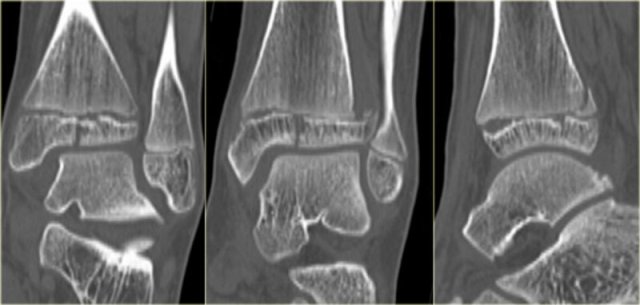

Here we have images of an extremely difficult case.

This woman had a distortion of the ankle and had pain on both medial and lateral side.

She was referred to the radiology department by her general practitioner.

The technician made the standard AP-, Mortise- and lateral view and showed them to the radiologist, who was a little bit puzzled.

First study the images and then continue reading.

The findings are:

• Soft tissue swelling both medial and lateral (red arrows).

Especially the medial swelling should make you consider a pronation exorotation injury (Weber C).

• Lucent line on Mortise view (black arrow) and lateral view. This should make you consider a tertius fracture.

The radiologist decided first to order a CT to find out if there really was a tertius fracture.

Continue with the CT and be amazed.

Scroll through the images.

It is amazing, that such a large tertius fragment is so difficult to see on the radiographs.

Also notice the soft tissue swelling on the medial side indicating rupture of the medial collateral ligaments (arrow).